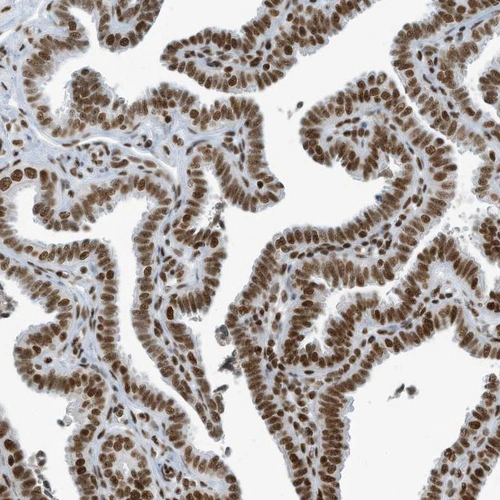

Immunohistochemical staining of human fallopian tube shows strong nuclear positivity in glandular cells.